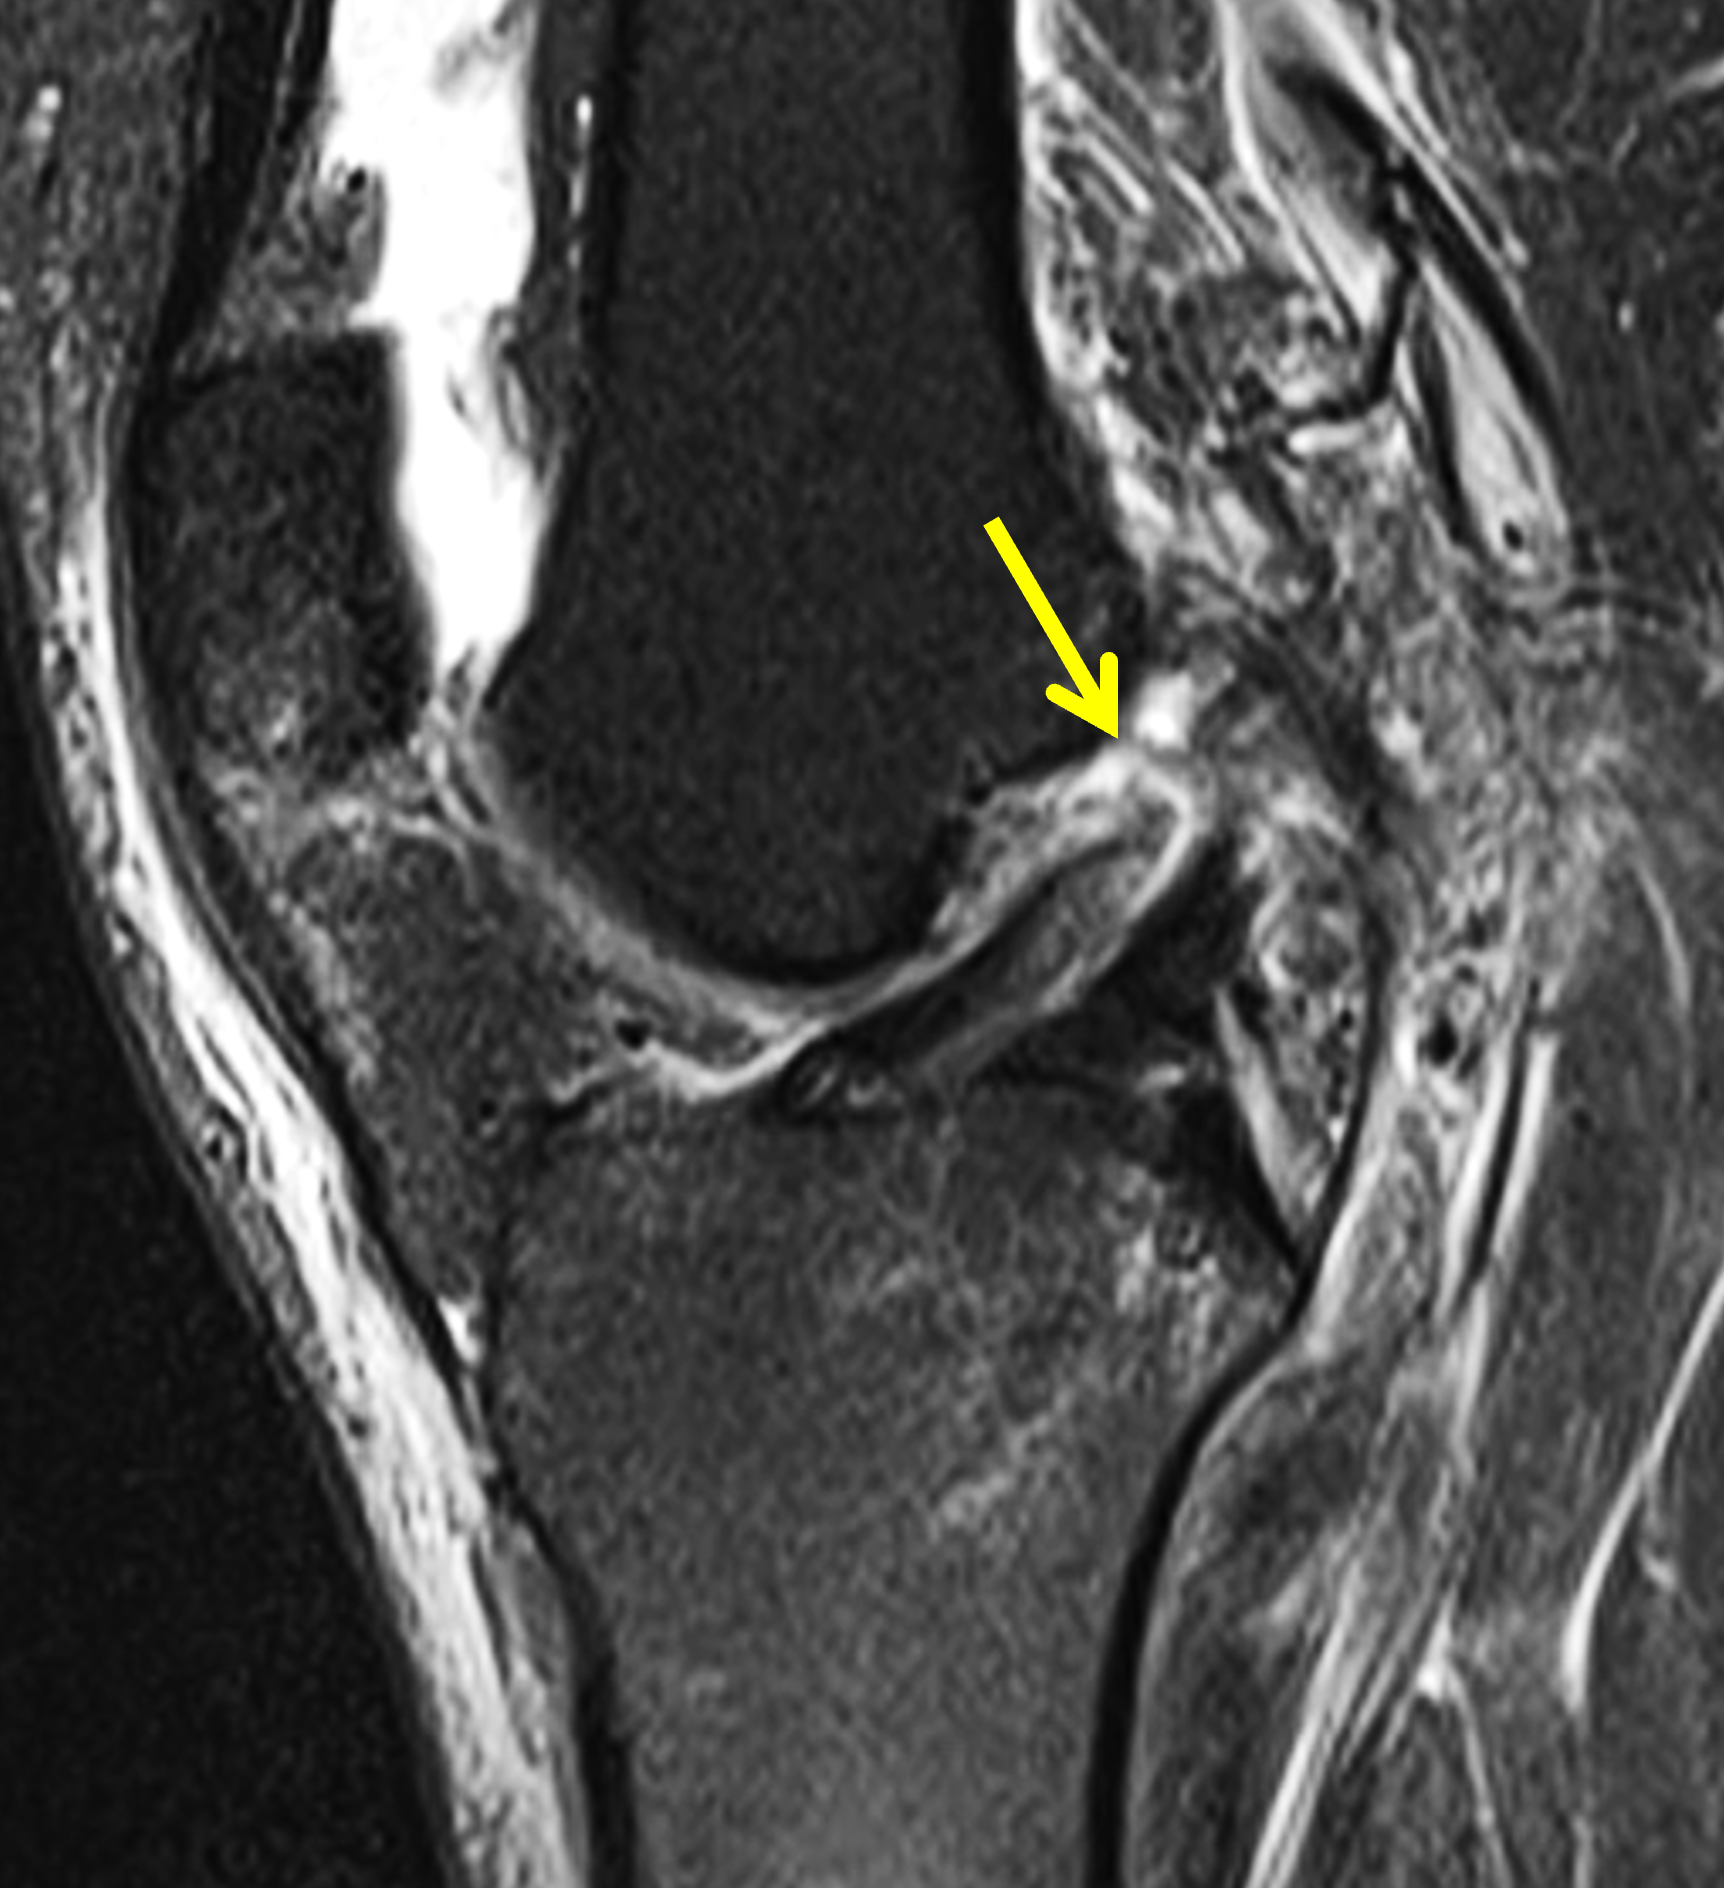

A 19-year-old collegiate baseball player sustained a twisting injury to the knee 3 weeks earlier. Sagittal (1A) proton density-weighted fat-suppressed image through the intercondylar notch, (1B and 1C) proton density-weighted images through the medial compartment, and (1D) fat-suppressed proton density image through the medial compartment are provided. What are the findings? What is your diagnosis?

Figure 2: (2A) Sagittal image through the intercondylar notch shows a complete tear of the anterior cruciate ligament (arrowheads). (2B and 2C) Near the posterior meniscocapsular junction of the medial meniscus, there is disruption of the posterior meniscotibial ligament (red arrow) and irregularity of the posterior meniscocapsular ligament (yellow arrow). (2D) On the fluid-sensitive sequence, linear high signal intensity is interposed between the ligaments and the posterior horn of the medial meniscus (arrowheads).

Anterior cruciate ligament tear with a medial meniscal ramp lesion.